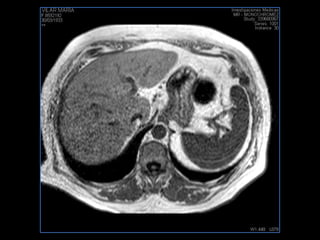

PROTOCOLO hígado graso AXIAL in phase y out phase AX T1 y AX fat sat +SAG T2  CON   GADOLINIO :  COR T1+AX T1(DIN) SAT: NO  FASE: RL THK: 4MM  COIL:  GAP: (FACTOR 1.4)  FOV: 40 CM NEX:2 SINCRONIZACION RESPIRATORIA EN 3 O 4 CICLOS ALE